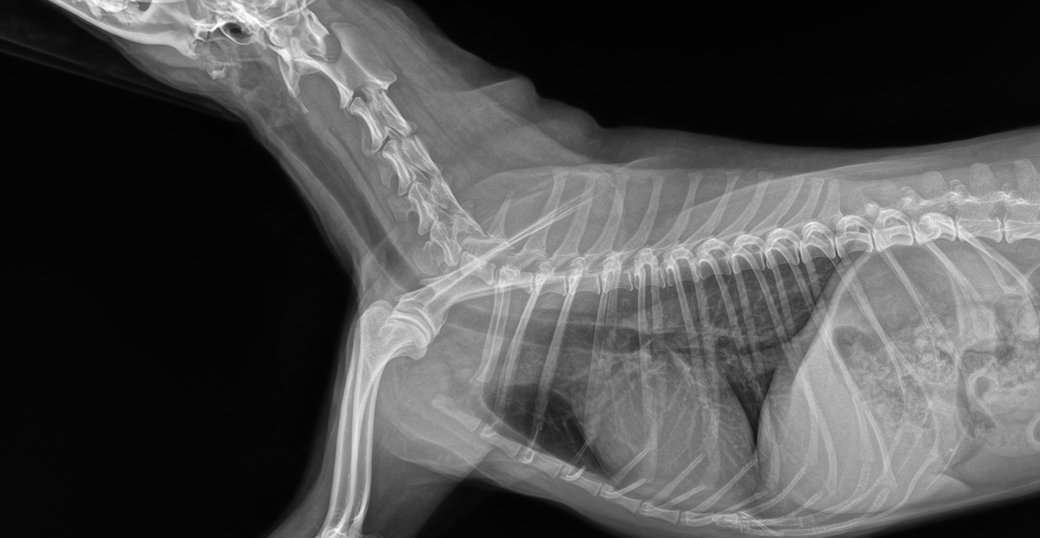

(6월 말입니다 사진 우측 화살표 클릭시 사진 커집니다)

공격적인 치료가 필요한 수준의 이상 상태는 아닌것으로 판단되니 환자를 직접 본 주치의의 판단을 따르시기 바랍니다. 또한 아래 사진처럼 경추 디스크 가능성이 있으니 이 부분에 대해서도 상담 받으시기 바랍니다.